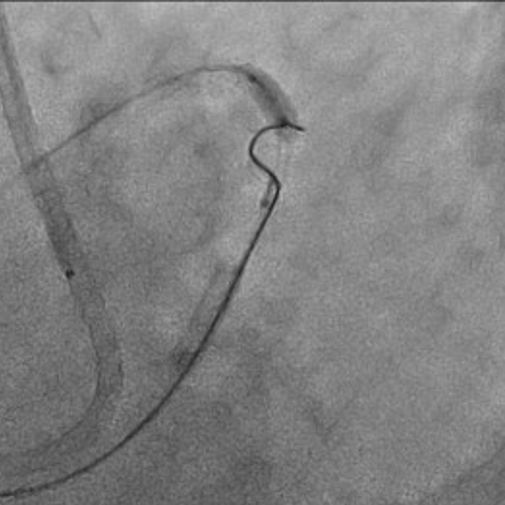

First, percutaneous coronary intervention (PCI) was performed toward the left anterior descending artery (LAD). The initial antegrade wire deviated from the true lumen; therefore, parallel wire technique was employed to achieve successful crossing. To avoid jailing the left circumflex artery (LCX) ostium, the stent was deployed precisely at the LAD ostium, and the left main trunk (LMT) was dilated using a 4.0-mm cutting balloon. One month later, intervention toward the LCX was undertaken. Intravascular ultrasound (IVUS) performed from the LAD confirmed achronic total occlusion (CTO) entry with a markedly thick plaque covering the LCX ostium. Although the lesion was accurately marked, penetration with a high-penetration guidewire was unsuccessful. Even with the balloon screen technique using a CP 8-20, wire penetration remained unsuccessful. Therefore, plaque debulking was selected to expose the CTO entry. Directional coronary atherectomy (DCA) was performed, and follow-up IVUS demonstrated significant plaquethinning compared with baseline. Subsequently, the CP 8-20 wire advanced smoothly, enabling successful wire crossing. The procedure was completed usinga mini-crush stenting strategy.